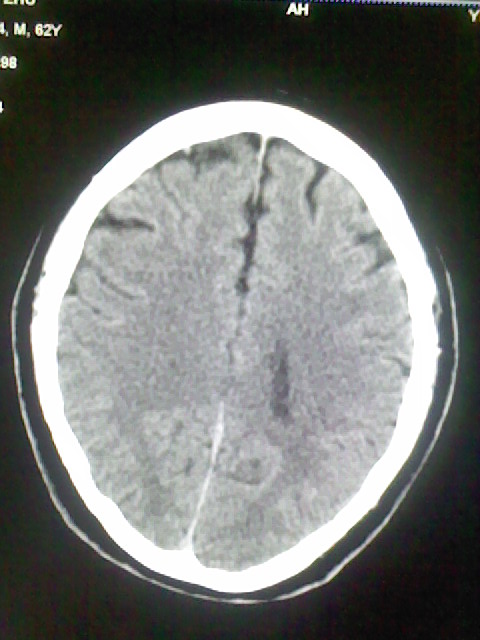

标题: CT15555:头痛 10余日 来诊大家帮忙看看 [打印本页]

标题: CT15555:头痛 10余日 来诊大家帮忙看看

脑萎缩

脑沟、裂增宽,提法脑萎缩,建议mt检查。

脑萎缩,以小脑为著。

脑沟、裂增宽,提示脑萎缩

老年脑

支持轻度脑萎缩。